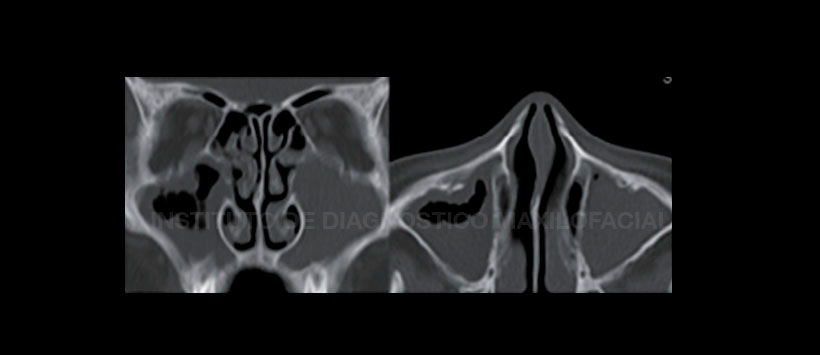

La tomografía computarizada se ha introducido como el estándar de oro para verificar los senos paranasales; sin embargo, considerando los altos niveles de radiación que reciben los pacientes, este método de diagnóstico solo debe usarse en circunstancias especiales.

Figura 1: Tomografía computarizada cone beam que muestra ocupamiento de ambos senos maxilares a predominio del lado izquierdo. Corte coronal y axial.